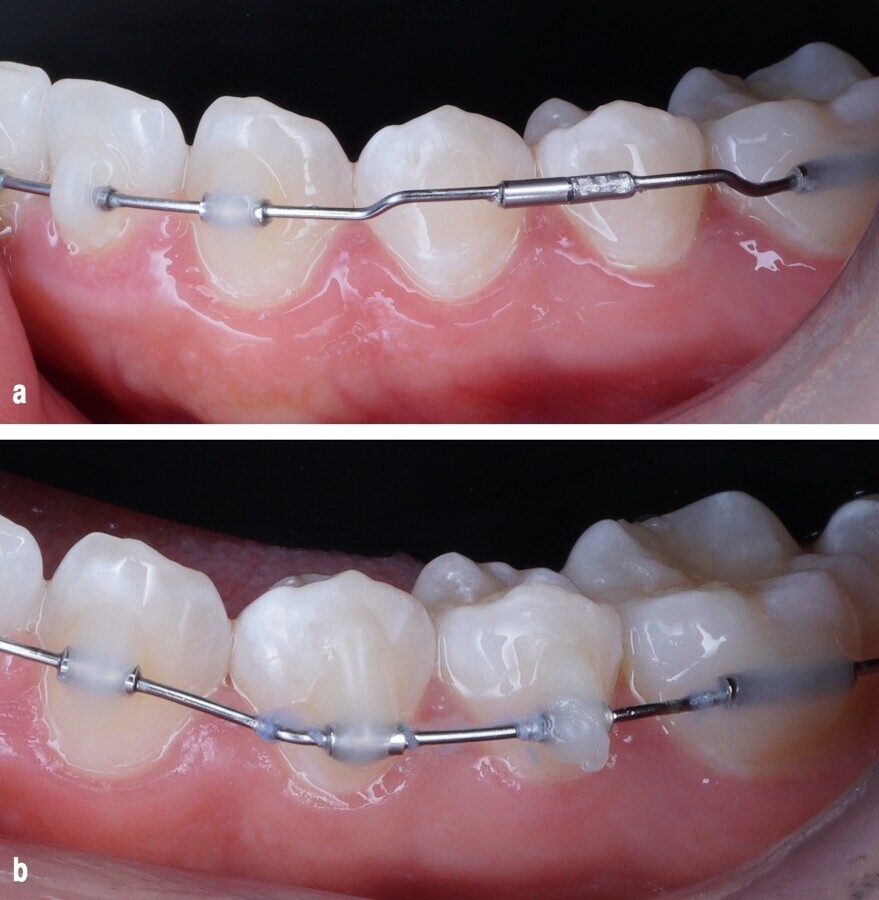

El desarrollo de tratamiento permite apreciar una mejoría en la alineación y nivelación dental, por lo cual pasamos a la última fase del tratamiento. En esta fase se pretende mejorar la nivelación del arco inferior. Para la corrección de la curva de Spee (Fig. 7), se realizaron dobleces en el arco hacia vestibular y oclusal, logrando una extrusión de los premolares inferiores sin el efecto indeseado de inclinación en sentido lingual (Fig. 8).

Figura 8. Doblez extrusivo (a) y compensatorio vestibular (b) en premolares inferiores del lado izquierdo.